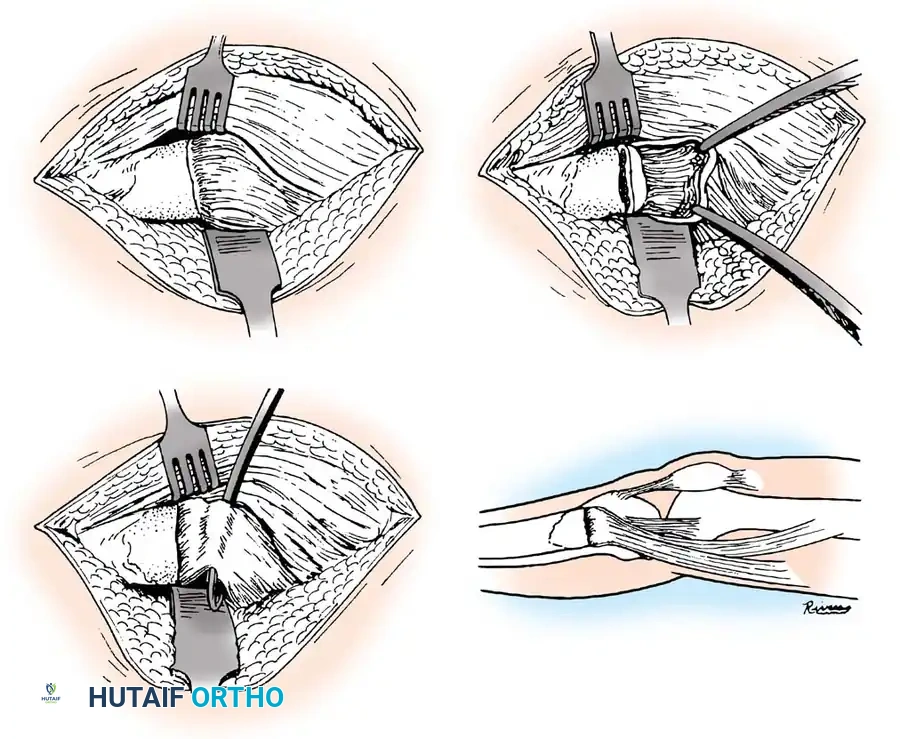

Intraoperative exposure demonstrating the parapatellar approach.

Elevation of the soft tissues to visualize the fracture hematoma.

3. Debridement and Joint Inspection:

* The Salter-Harris III or IV injury is frequently a tongue-type fracture anteriorly, with the entire tibial tuberosity elevated and hinged posteriorly.

* Dissect medially and laterally into the joint capsule until the intra-articular physeal fracture line is visualized.

* Elevate the entire physeal fragment gently. Irrigate the joint copiously to remove hematoma and osteochondral debris.

* Critically, extract any interposed soft tissues (such as torn periosteum or the anterior horn of the meniscus) from the fracture site, as these will mechanically block reduction.

Removal of interposed periosteum from the fracture site.

Direct visualization of the articular surface to ensure anatomic reduction.

4. Reduction:

* Reduce the fracture anatomically. The motion should mimic closing a book or a hinge.

* Extend the knee; if the reduction springs open or feels elastic, soft tissue entrapment is still present and must be addressed.

* Confirm joint congruity visually and via fluoroscopy.

Fluoroscopic confirmation of anatomic reduction prior to definitive fixation.